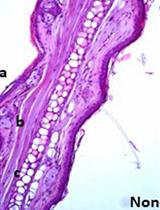

Alterations in diet and gut microbial ecology underlie the pathogenesis of type 1 diabetes (T1D). In the non-obese diabetic (NOD) mouse, we found high concentrations of bacterial metabolites acetate and butyrate in blood and faeces correlated with protection from disease. We reconstituted germ free (GF) NOD mice with fecal bacteria from protected NOD mice fed with high acetate- and butyrate-yielding diets, to test whether the transferred gut microbiota protect against the development of T1D. GF NOD mice that received a microbiota shaped by high acetate- but not butyrate-yielding diet showed a marked protection against diabetes. This fecal transplantation assay demonstrated the potential for a dietary technology to reshape the gut microbiota that enables specific bacteria to transfer protection against T1D.

Changes in the gut microbiota have been observed in a wide variety of illnesses and conditions. A dysbiotic gut microbiota loses homeostatic balance due to changes in the ratios between commensal and pathogenic bacteria. Dysbiosis can be observed when there are large changes in the makeup of the microbiota, with certain species increasing or decreasing in number (Clemente et al., 2012; Rajilic-Stojanovic, 2013). Moreover changes in gut microbiota composition (which may affect metabolites such as SCFAs) associate with many inflammatory diseases (Clemente et al., 2012), including T1D (de Goffau et al., 2013; Endesfelder et al., 2014). For example, patients with, or people who are predisposed to, autoimmune type 1 diabetes typically show a decrease in Firmicutes abundance and an increase in their Bacteroidetes abundance (Giongo et al., 2011). In contrast, various types of inflammatory bowel diseases (IBD), such as ulcerative colitis or Crohn’s disease show the opposite (Frank et al., 2007; Spor et al., 2011). One possibility for treatment of T1D is the use of beneficial bacteria, following their identification and successful trialing. For example, Lactobacillus johnsonii isolated from diabetes resistant rats was able to prevent T1D development in the spontaneous rat model of T1D (Valladares et al., 2010). Likewise, transfer of microbiota from male mice, who are less prone to develop T1D, to female mice reduced their rates of T1D, which correlated with changes in the mouse’s hormone levels (Markle et al., 2013). We used diets that reshape the gut microbiota composition and induced the release of microbial short chain fatty acids (SCFAs). In this study, we have demonstrated that particularly the SCFA acetate and butyrate reduced the onset of T1D in NOD mice (Marino et al., 2017). We wanted to determine if the protective effect was coming directly from the bacteria, or by the produced microbial SCFA acetate or butyrate. We therefore have developed a protocol to harvest the microbiota from diet-fed NOD mice, and transfer it to GF NOD mice, so that we can examine the effects of the altered microbiota and its metabolites on the pathogenesis of T1D.